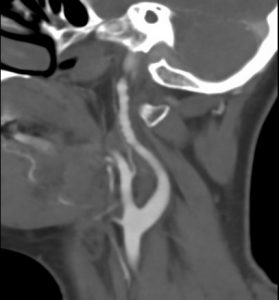

Fibromuscular dysplasia in the cervical arteries can be asymptomatic or cause neurological syndromes. These range from a whooshing in ear sounds to hemispheric stroke to a multitude of non-specific signs and symptoms. Sometimes a carotid bruit is the impetus for the diagnosis. Other times, the diagnosis follows an incidental finding that is discovered after carotid imaging is performed for some other reason. Cervical FMD can be extra or intra-cranial. Extra-cranial carotid artery involvement in FMD is usually in the distal artery, at the level of C1-C2. The prevalence of this involvement may be higher than previously thought according to the international registry of fibromuscular dysplasia. When extracranial FMD is present, intracranial involvement is also prevalent.

Imaging of cerebral FMD can be done with duplex ultrasonography (that has a low sensitivity / specificity in this site), CT angiography or MR angiography. Notably, FMD patients should undergo at least one brain imaging. A 2017 analysis of the FMD registry has shown that 12.9% of women with fibromuscular dysplasia have brain aneurysms. Of these over 40% are larger than 5mm. Thus, identifying these aneurysms matters.